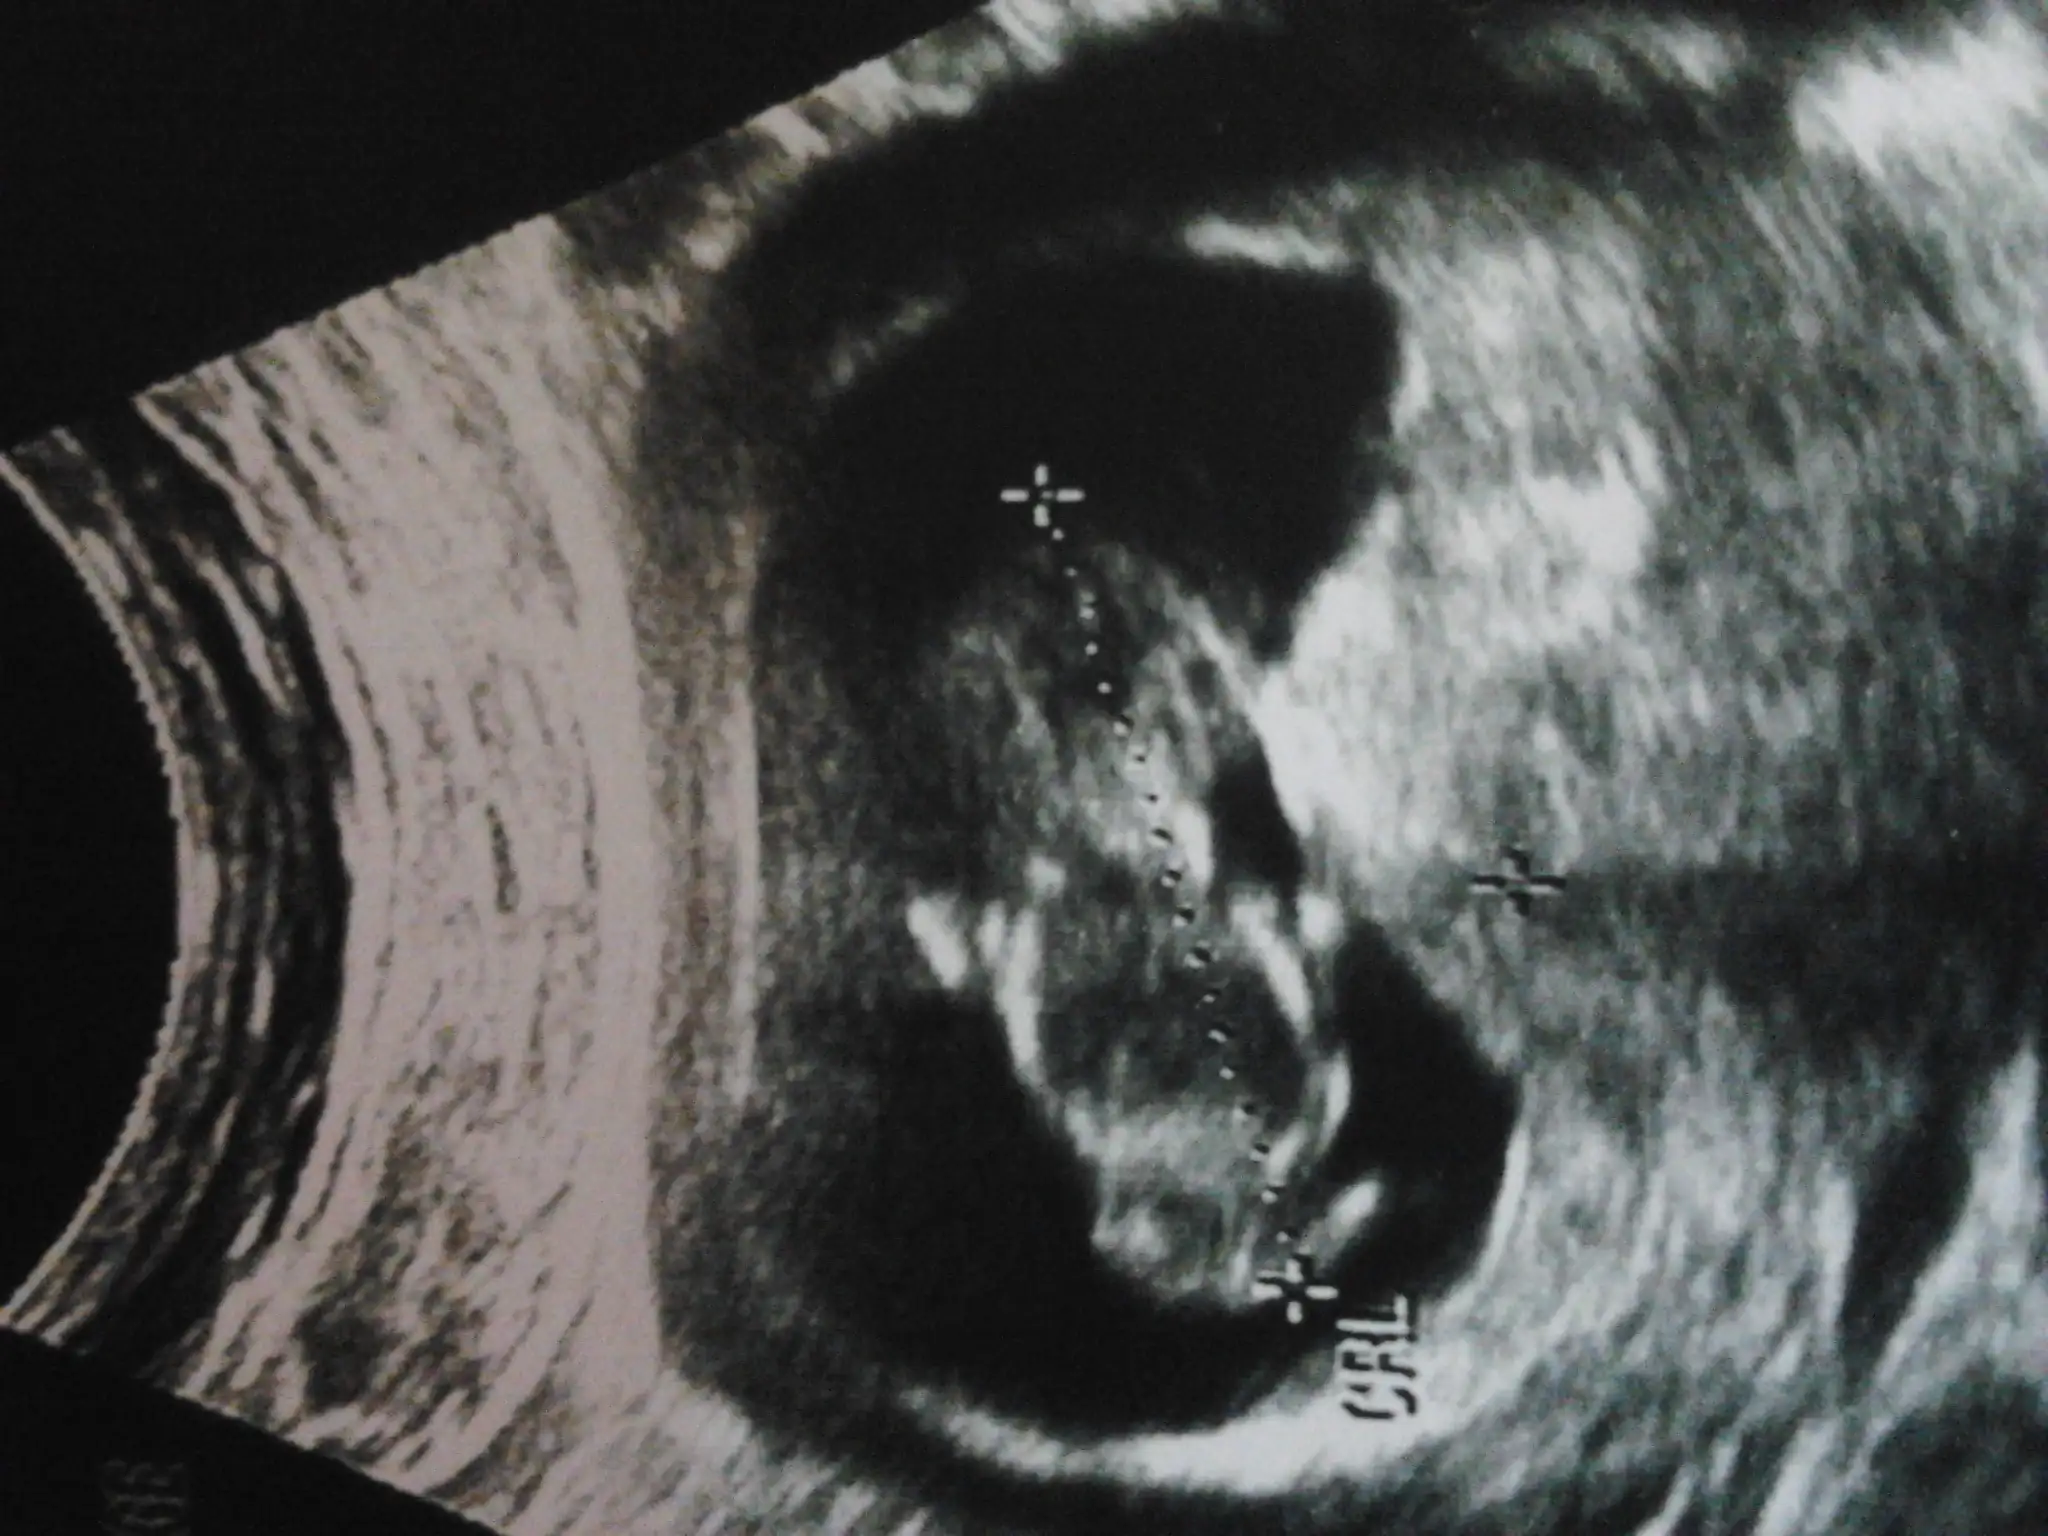

Kizlar 12haftaligim bi yorum yapabilirmisiniz? Cok merak ediyiruz simdiden cok tesekkurler

Kızlar benim bebiş 12haftalık oldu dr cinsiyetıni söyleyemedi anlayan arkadaşlar yorum yapabilirmi

kizlar bugun kanama yuzunden tekrar hastanedeydim tam 1 hafta oluyor resmi koyali doktorum bugun erkege cok benziyo degismez heralde dedi? yukarda resim ne diyosunuz? tekrar yukliyimmi resmi?